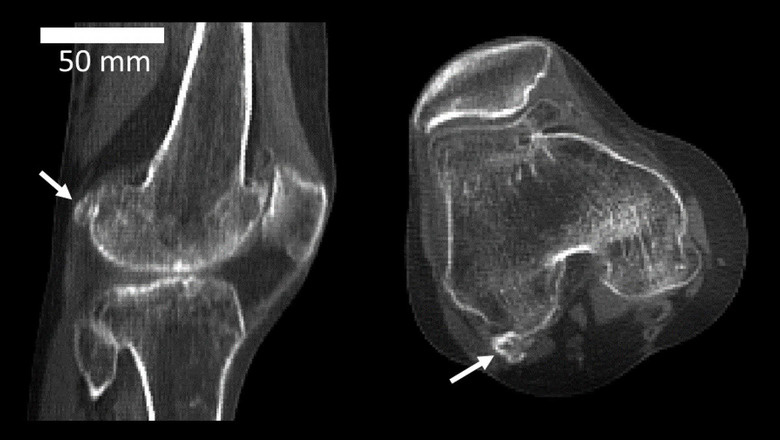

Сравнение задней части колена человека (слева) и макаки (справа), на котором видны медиальная и латеральная фабеллы у макаки и латеральная фабелла у человека. Фото: доктор Майкл Бертаум и Имперский колледж Лондона.